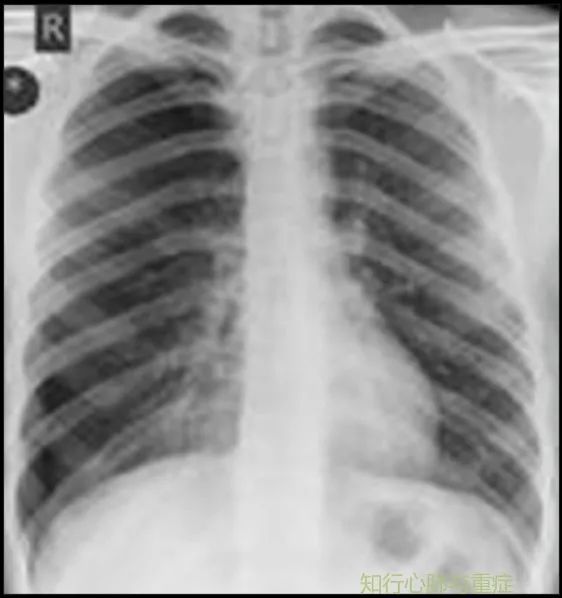

Dejene, S等在2013年报道了一名26岁的油漆工(有长期吸烟史)吹了26个生日气球后不久出现严重的右侧胸痛和呼吸困难的病例(影像显示右侧大面积气胸)。